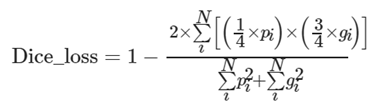

在脑肿瘤检测网络最后的输出层,输出与输入脑肿瘤数据维度相同的脑肿瘤分类概率图,表示每一个体素点是否为脑肿瘤的概率.脑肿瘤检测网络是通过损失函数来计算输出值和标签值之间的误差值,根据误差值来进行网络的反向参数修正,以获得脑肿瘤检测网络最佳的权值和偏置值.在自然图像的目标检测和目标分割任务中,常用的损失函数为Dice_loss,其计算公式为:

在三维MRI脑肿瘤影像中,由于医学影像具有特殊性,与自然图像相比,在整幅脑肿瘤影像中,脑肿瘤病灶区域占比较小,非病灶区域的占比更大.若采用传统的Dice相关性系数作为损失函数,在网络训练过程中,导致网络趋向于对非脑肿瘤病灶区域的特征学习,无法有效提取脑肿瘤病灶区域的特征,从而造成误检和漏检的情况.因此为了提高网络对脑肿瘤区域的学习能力,对传统的Dice_loss损失函数进行了改进,改进后的损失函数计算公式为:

从式(9)可知,由于gi部分对应的是脑肿瘤病灶区域,采用对gi部分进行权值加权,将预测结果和金标准在损失函数中的占比分为1:3.通过加权的方法,损失函数对金标准分配的损失系数更大,能够加强网络对脑肿瘤病灶区域的特征学习,弱化网络对非肿瘤区域的损失值分配,减小了脑部MRI背景影像对病灶区域特征学习的干扰,从而提高网络的检测准确率.